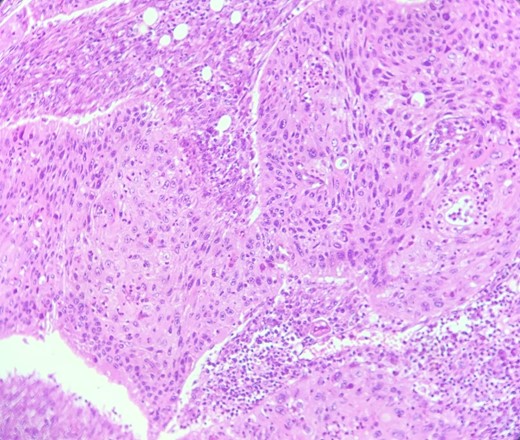

Mr. B. is a 59-year-old patient with no notable pathological history, presenting with melenas associated with marked weight loss. A fibroscopy revealed a thickened and ulcerated gastric mucosa. Abdominal and pelvic CT scans revealed a tissue process in the body and tail of the pancreas invading the splenic hilum, adjacent vessels ans gastric wall, measuring 11 cm long (Fig. 5). A caudal spleno-pancreatectomy enlarged to the colon, omentum and stomach was performed. Macroscopically, the tumor had a grayish–white appearance, poorly limited and indurated on palpation. Histologically, it was a well-differentiated, keratinizing squamous cell carcinoma of the tail of the pancreas (Figs 6 and 7), infiltrating the splenic hilum, gastric wall and colon.

HE section: Neoplastic cells have densely chromatic enlarged nuclei with prominent nucleoli. They are enlarged with abundant eosinophilic cytoplasm and focal keratinization. Intercellular bridges are slightly visible (x200).